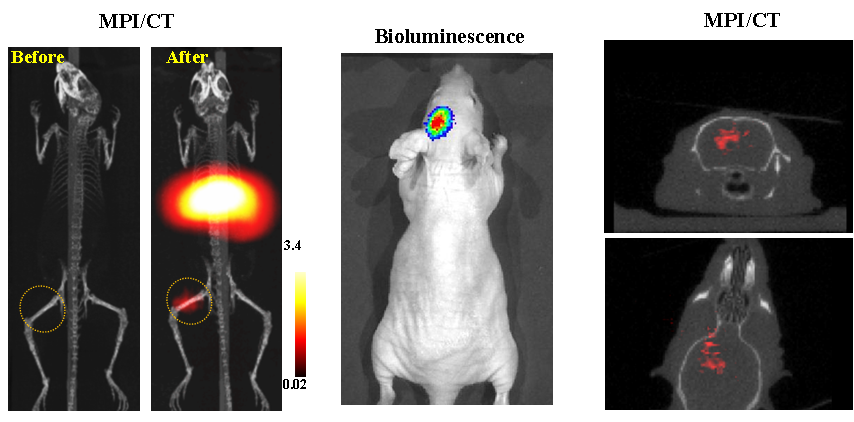

今年二月份,宋国胜教授与斯坦福大学饶江宏教授合作,通过系统的研究获得了影响磁性粒子成像信号的作用规律和关键原理,开发了新型磁性粒子探针---FeCo合金粒子,并首次应用于磁性粒子成像(MPI)。该造影剂在极低含量时(5 ng)仍具有很强的造影效果。这意味着,未来在进行人体成像时,可以使用更小剂量的造影剂,从而避免高剂量造影剂引起的肾肝损伤。基于MPI的直接成像原理,我们可以对造影剂进行正相和无背景干扰的活体成像,极大地提高信噪比。这项技术为肿瘤早期诊断、癌细胞示踪、脑中风、药物输送治疗、肺部灌注成像、胃肠出血、神经退行性疾病、磁热治疗等在活体中的可视化研究,提供了强有力的手段。相关研究成果以tyc1286太阳成集团为第一单位发表在Nature 子刊《Nature Biomedical Engineering》。该期刊是“生物医学工程”的顶级期刊。宋国胜教授为该论文的共同通讯作者。